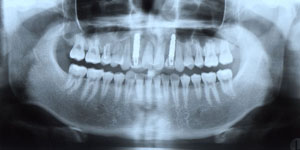

교정치료 후 debonding과 함께 상악 6전치 설측면에 .0195 twistflex를 사용한 lingual bonded retainer를 부착하였다. space closure와 함께 gingival bunching이 중절치 부위에 나타나 있음으로 충분히 기다린 후 (6개월 정도) 최종 보철물을 시행하기로 계획하였다.

최종 보철물 시행 시 필요하면 양 중절치  부위에 치은성형술 개념의 gingivectomy를 시행하고 다음과 같은 보철 치료를 계획하였다 (그림 7,8).

그림 7. 증례환자의 교정치료 후 모습으로 차후 중절치 부위의 치은성형술과 함께, 측절치 임시보철물의 근심면 삭제 후 중절치의 라미네이트 수복(폭경은 1mm, 장경은 2mm 증가) 그리고 측절치의 최종보철로 심미적 보철물을 기대할 수 있다.

그림 8. 증례환자의 교정치료 후 측모두부방사선사진과 파노라마 사진